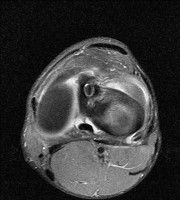

무릎 mri 간단히 봐주실 수 있으시나요 ㅠㅠ

안녕하세요 8년전 십자인대 수술하고 최근 무리한 운동에 무릎 불편감이 생겨서

mri 찍었습니다.

진단결과는 첫 찍은 병원에서 활액막염 이라는 진단을 받았습니다. 혹시 봐주실 수 있으실까요?

올라온 MRI가 단편적이라서 정확한 진단에 어려움이 있지만 십자인대에는 큰 이상이 있지는 않은것 같으며, 무릎관절내 물이 있는 것으로 보아 활액막염의 진단이 맞을 것 같습니다.

하지만 단편적인 영상이기 때문에 촬영병원에서 정확한 판독지 등을 받으시는 것이 좋겠습니다.